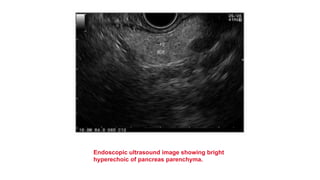

Endoscopic ultrasound image showing bright

hyperechoic of pancreas parenchyma.

• Fat accumulation in the pancreas, defined as fatty pancreas, is usually an

incidental finding during transabdominal ultrasound examination.

• Fatty pancreas without any significant alcohol consumption is defined as non-

alcoholic fatty pancreas disease